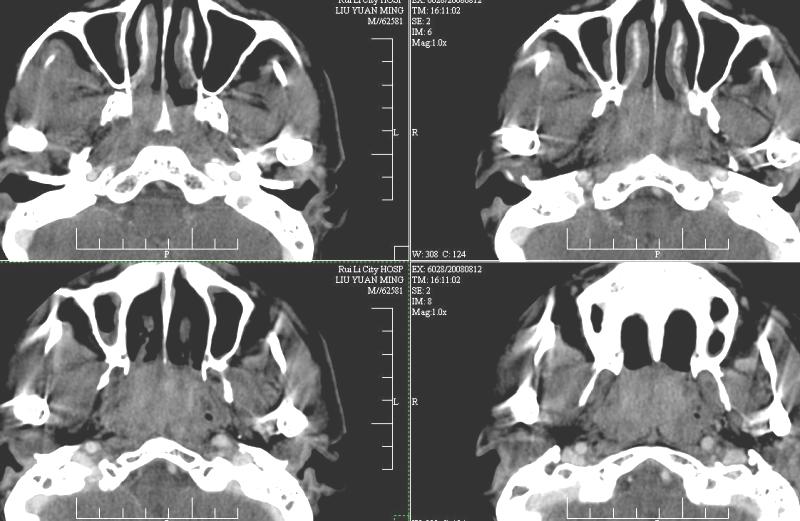

以下是引用ydx_74在2008-8-12 22:09:00的发言:[br]不考虑鼻咽癌。没有淋巴结肿大,没有颅底骨质破坏,咽隐窝、咽鼓管咽口存在,咽旁间隙清楚,平扫ct值34hu,增强动脉期81hu,实质期约85hu,增强幅度达50多,除外增强时机没有掌握好因素,可以考虑鼻咽纤维血管瘤吗?